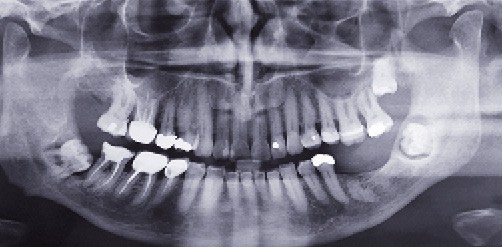

Une dent en rétention est une « dent immature non présente sur l’arcade, à l’âge où elle aurait dû faire son éruption ». Sans traitement, elle peut, en devenant mature, devenir enclavée ou incluse (fig. 1).

Une dent incluse proprement dite est « une dent encore incluse dans l’os maxillaire ou mandibulaire dont l’édification radiculaire apicale s’est terminée avant que le processus d’éruption ne lui ait permis d’évoluer jusque dans le milieu buccal, sans la moindre effraction de la muqueuse orale et sans contamination du sac péricoronaire par la flore bactérienne buccale » (fig. 2). Une dent en désinclusion est définie comme une « dent restée incluse, une grande partie de la vie, jusqu’à ce que certaines transformations morphologiques de la cavité orale favorisent son exposition au milieu buccal » (fig. 2).

Une dent enclavée (terme utilisé principalement en France) est « une dent dont l’édification radiculaire apicale s’est terminée après que le processus d’éruption…